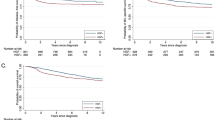

In the Carolina Breast Cancer Study, 32% of participants were classified as HGF-positive by our 38-gene assay. Clustering the HGF signature genes across all of the CBCS patients, we found two main gene clusters that corresponded well with expression patterns from the original reference signature [9]. Specifically, HGF-positive tumors had few (n = 6) genes highly expressed, while most genes had a characteristic pattern of lower expression (Fig. 1). TNBC samples were enriched in the HGF-positive cluster.